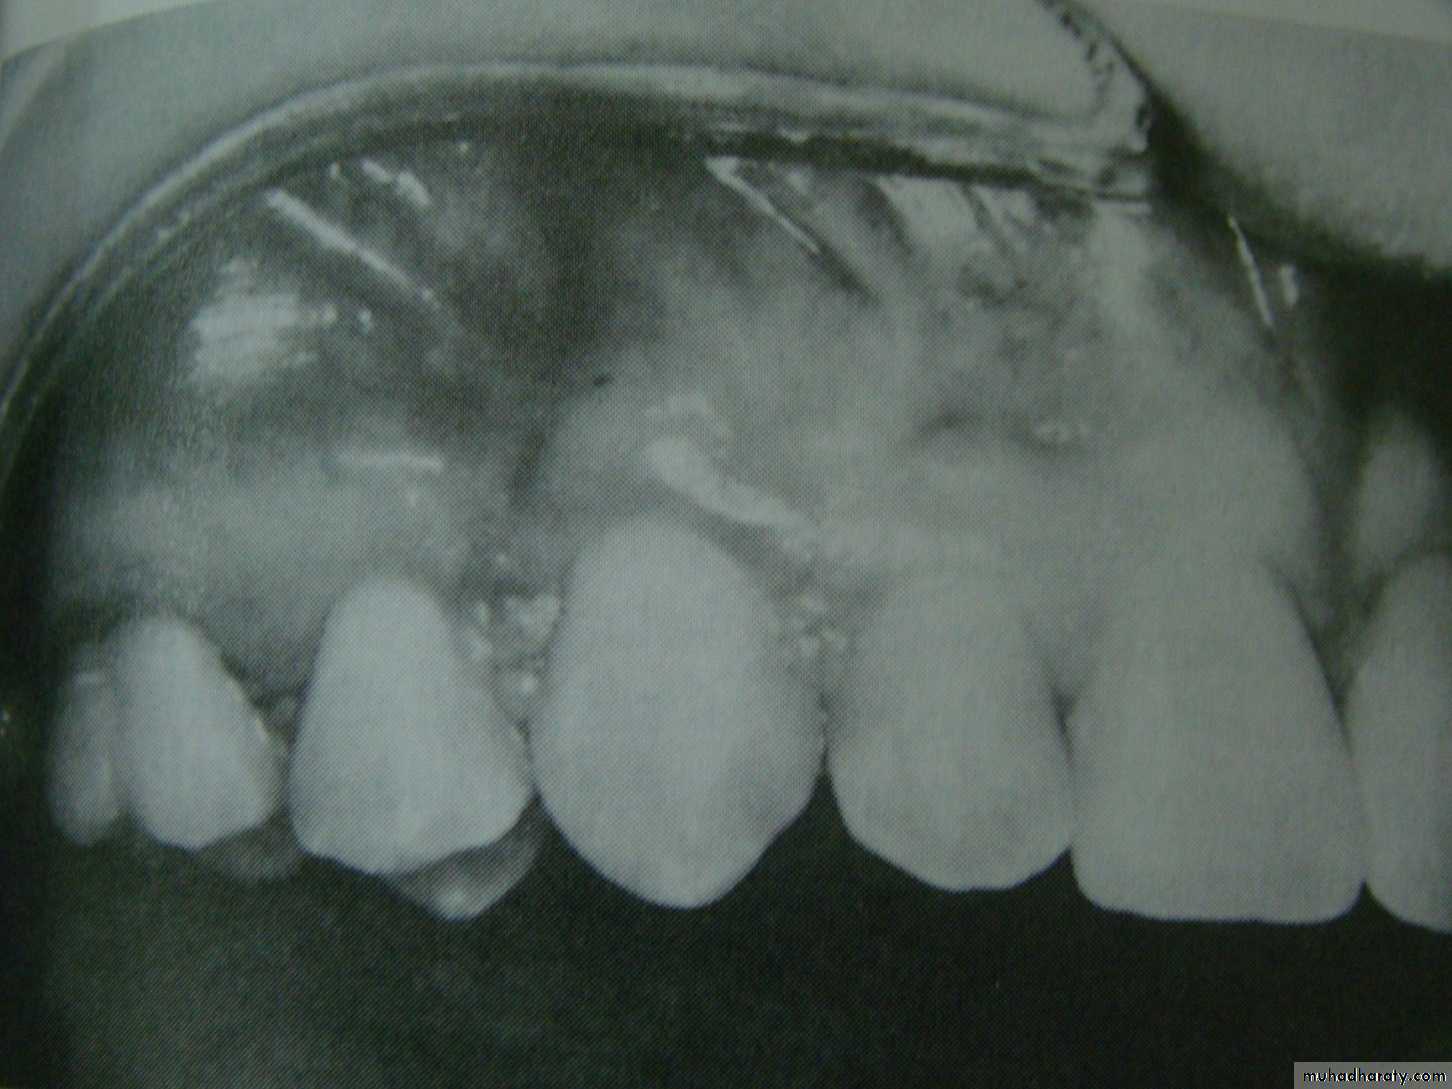

Radiological examination

The periapical radiograph provide a detailed picture of the tooth and its surroundings and is helpful for demonstrating the degree of root formation of the canine , apical curvature , the existence of any root resorption affecting the adjacent lateral incisor and the presence of an associated cyst .Mosul university- College of dentistry-oral & maxillofacial surgery department

The relative radiopacity of the crown of the impacted canine may assist in the determination of the tooth position (the more radiopaque lie palataly )

The occlusal views are 3 types ,anterior , vertex , and true . the vertex occlusal technique is the only technique used for determination of the true position of the impacted tooth.

the anterior occlusal radiograph is taken the x ray tube is sited at the nasion

the vertex occlusal view the x ray tube is arranged so that the central ray passes along the long axis of the central incisors

the true occlusal view is taken with x ray tube positioned so that the central ray is at right angle to the film

Parallax method in this technique a periapical radiograph of the area is taken and the x ray tube is then moved in either mesial or distal direction before a second periapical film is taken .the two radiograph is then compared and if the impacted tooth seen to move in the same direction as the x ray tube it is lying palataly , whilst if it moves in the opposite direction it is lying labially.